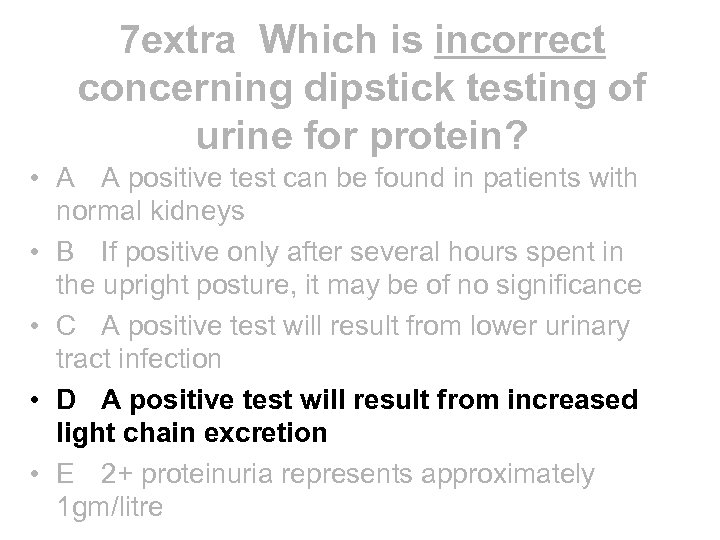

7 extra Which is incorrect concerning dipstick testing of urine for protein? • A A positive test can be found in patients with normal kidneys • B If positive only after several hours spent in the upright posture, it may be of no significance • C A positive test will result from lower urinary tract infection • D A positive test will result from increased light chain excretion • E 2+ proteinuria represents approximately 1 gm/litre

7 extra Which is incorrect concerning dipstick testing of urine for protein? • A A positive test can be found in patients with normal kidneys • B If positive only after several hours spent in the upright posture, it may be of no significance • C A positive test will result from lower urinary tract infection • D A positive test will result from increased light chain excretion • E 2+ proteinuria represents approximately 1 gm/litre

7 extra Which is incorrect concerning dipstick testing of urine for protein? • A A positive test can be found in patients with normal kidneys • B If positive only after several hours spent in the upright posture, it may be of no significance • C A positive test will result from lower urinary tract infection • D A positive test will result from increased light chain excretion • E 2+ proteinuria represents approximately 1 gm/litre

7 extra Which is incorrect concerning dipstick testing of urine for protein? • A A positive test can be found in patients with normal kidneys • B If positive only after several hours spent in the upright posture, it may be of no significance • C A positive test will result from lower urinary tract infection • D A positive test will result from increased light chain excretion • E 2+ proteinuria represents approximately 1 gm/litre